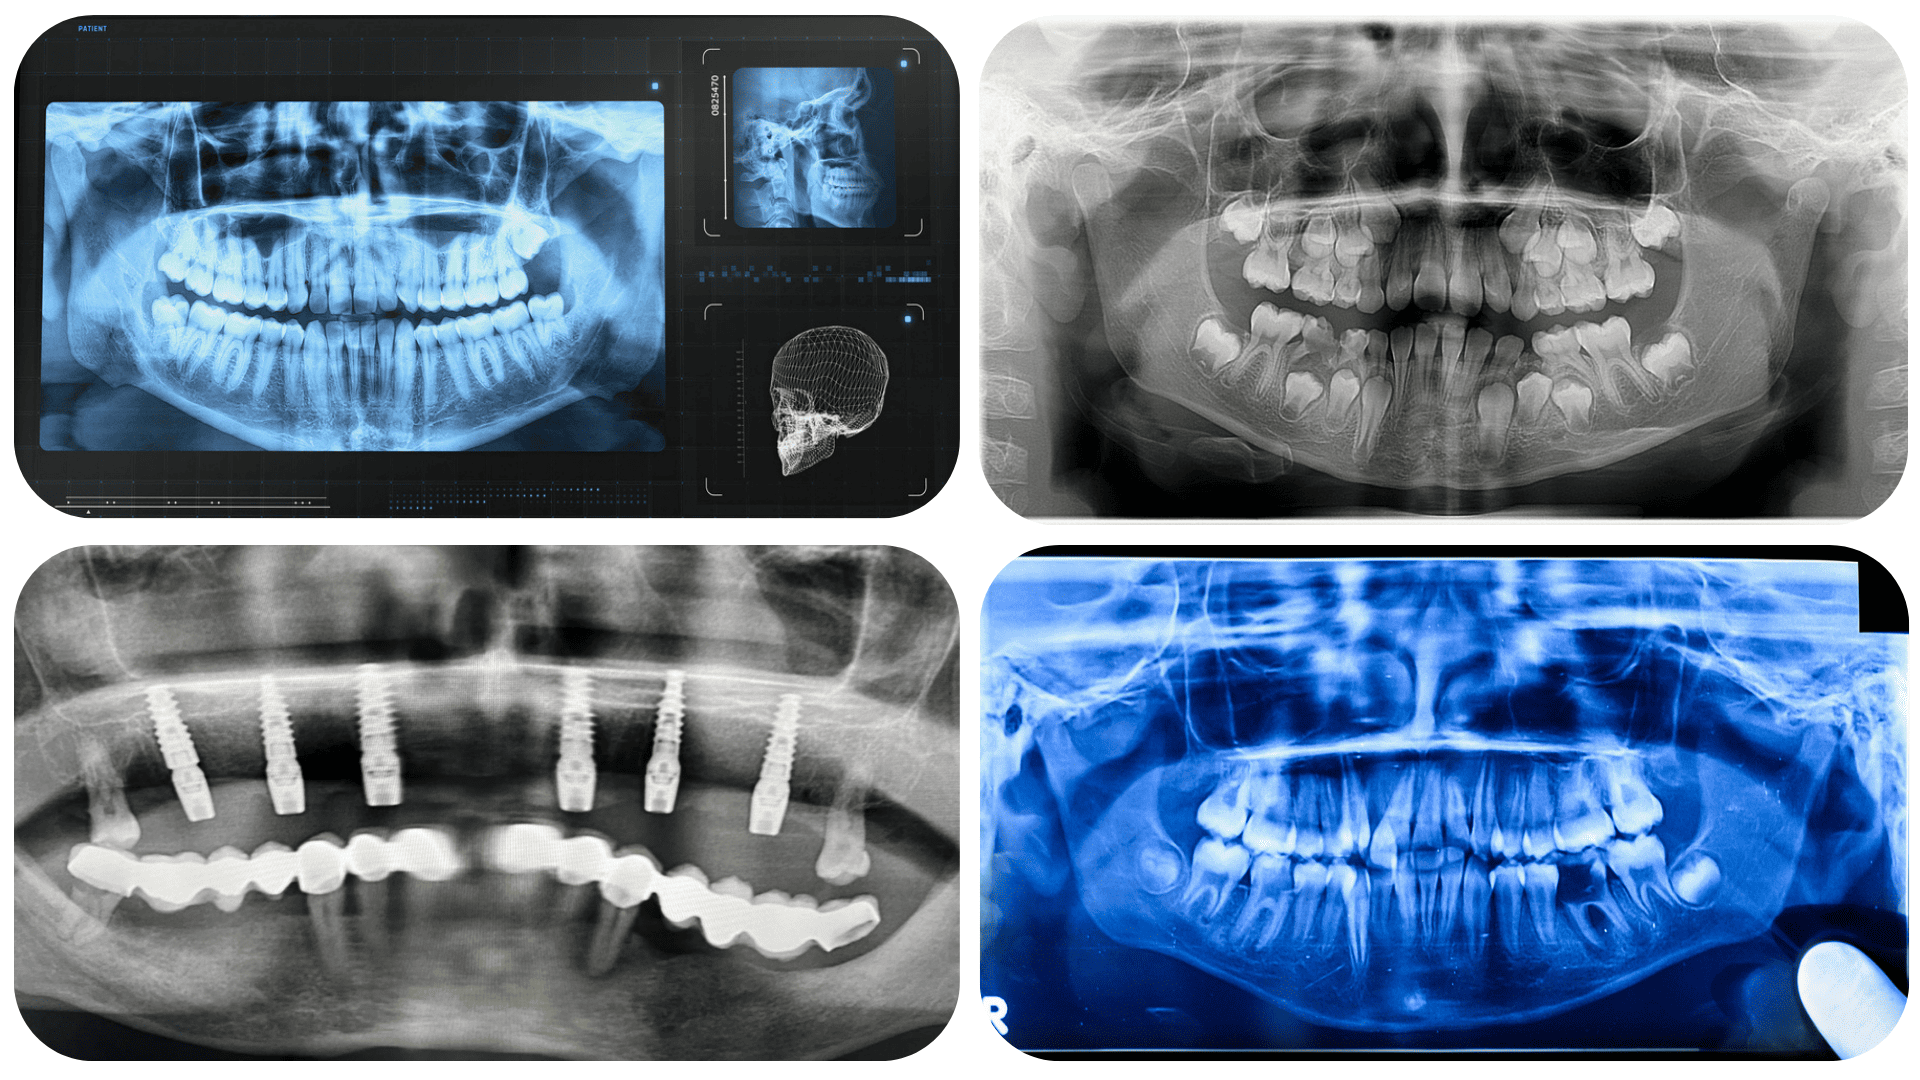

ORTOPAN

(PANORAMSKI RADIOGRAM)

Ortopan mogućuje cjelovit pregled zuba, čeljusti i okolnih struktura na jednoj snimci. Idealan je za procjenu stanja zuba, kosti, zubnih zametaka i promjena koje nisu vidljive kliničkim pregledom, te je temelj svake kvalitetne dentalne dijagnostike.